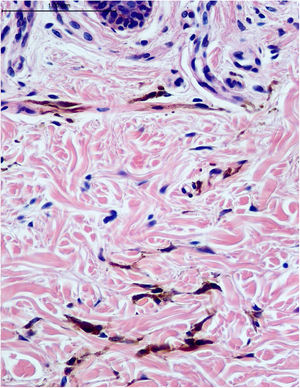

Relatamos o caso de paciente do sexo feminino, branca, de 48 anos, apresentando máculas castanho‐acinzentadas de aspecto rendilhado na palma da mão direita há 20 anos. Ao exame, havia predomínio nas dobras palmares da base do 3°, 4° e 5° quirodáctilos (fig. 1). Mais recentemente (dois a três anos), surgiu quadro semelhante, mais discreto, no dorso da mesma mão (fig. 2). Assintomáticas. Não foram encontrados fatores desencadeantes e de lesões semelhantes contralaterais ou em qualquer outra localização. Paciente não menopausada; negava uso de anticoncepcional oral. Ausência de comorbidades e histórico familiar. Realizada biópsia incisional na palma, que revelou proliferação esparsa e mal delimitada de células fusiformes com grande quantidade de melanina, em disposição perivascular e intersticial na derme reticular (figs. 3 e 4). As células foram positivas para os anticorpos anti S‐100, HMB‐45 e Melan‐A em reação imuno‐histoquímica, concluindo tratar‐se da proliferação de melanócitos.

Histologicamente, os melanócitos são células localizadas na camada basal da epiderme, e o diagnóstico de melanocitose dérmica baseia‐se na presença de melanócitos dendríticos na derme.7 Melan‐A, S‐100 e HMB‐45 demonstram boa especificidade para lesões melanocíticas, podendo ser usados para avaliar a maturação dos melanócitos e ser potenciais marcadores no diagnóstico da MDA.8 A relação da MDA com melanoma encontra‐se raramente discutida na literatura.9